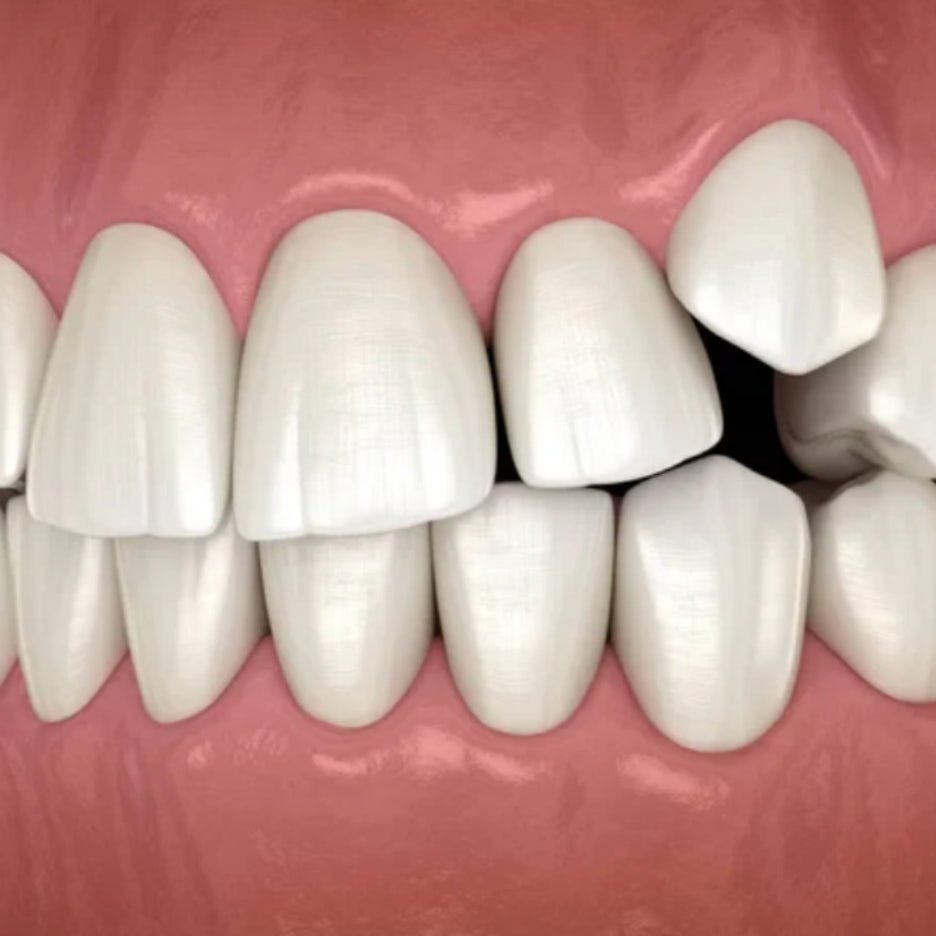

반갑습니다. 안산투명교정 치의학 박사 장영준입니다. 아마 이 글을 읽고 있다면, 흔히 말하는 ‘철길’을 남들에게 보여주기 싫은 분들이 대부분일 텐데요. ‘철길’이란, 브라켓 교정 장치가 마치 철로